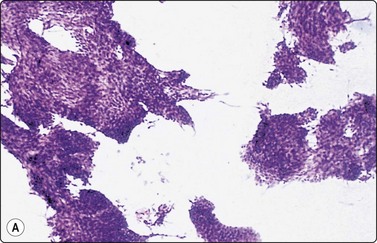

Dermatofibrosarcoma protuberans (DFSP) (Fig. 14.30)

The cytological findings in DFSP have been reported by Domanski and Gustafson.74 The yield is abundant of both tissue fragments of variably cohesive spindle cells and dispersed single cells and stripped nuclei. There is moderate anisokaryosis, but the nuclear chromatin is granular and nucleoli are small. A streaming arrangement that vaguely suggests a storiform pattern may be seen. The tumor cells stain positively for vimentin and CD34. The main differential diagnoses are low-grade fibrosarcoma and monophasic fibrosarcoma-like synovial sarcoma. The clinical presentation is an important clue to diagnosis

image image image

Fig. 14.30 Dermatofibrosarcoma protuberans (DFSP)

(A) Dispersed single cells and stripped nuclei with moderate anisokaryosis, but granular nuclear chromatin (MGG, MP); (B) A streaming arrangement that vaguely suggests a storiform pattern may be seen (MGG, MP); (C) The tumor cells stain positively for CD34 (cell block preparation, CD34).